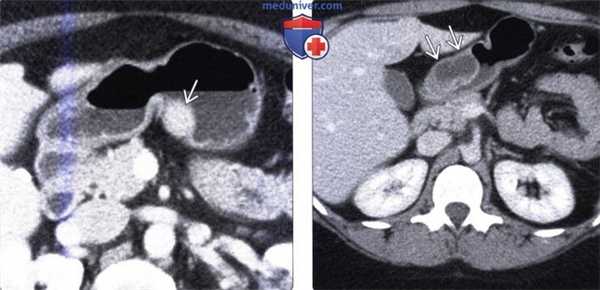

(Слева) На аксиальной КТ с контрастным усилением визуализируется объемное образование в стенке тела желудка. Образование накапливает контраст так же, как ПЖ в норме. Путем эндоскопической биопсии была подтверждена эктопическая ткань поджелудочной железы.

(Справа) На аксиальной КТ с контрастным усилением у пациента с жалобами на боль в животе визуализируется кистозное образование в стенке дистальных отделов желудка, как выяснилось после операции — эктопическая ткань поджелудочной железы. В зависимости от соотношения ацинусов, протоков и островковых клеток эктопическая ткань поджелудочной железы может выглядеть однородной или неоднородной, или даже кистозной.

(Справа) На аксиальной КТ с контрастным усилением у пациента с жалобами на боль в животе визуализируется кистозное образование в стенке дистальных отделов желудка, как выяснилось после операции — эктопическая ткань поджелудочной железы. В зависимости от соотношения ацинусов, протоков и островковых клеток эктопическая ткань поджелудочной железы может выглядеть однородной или неоднородной, или даже кистозной. (Слева) На рентгенограмме верхних отделов ЖКТ визуализируется небольшое объемное образование в стенке антрального отдела желудка, слизистая которого не изменена. Центральная «точка» обусловлена наличием рудиментарного протока, заполненного бариевым контрастом.